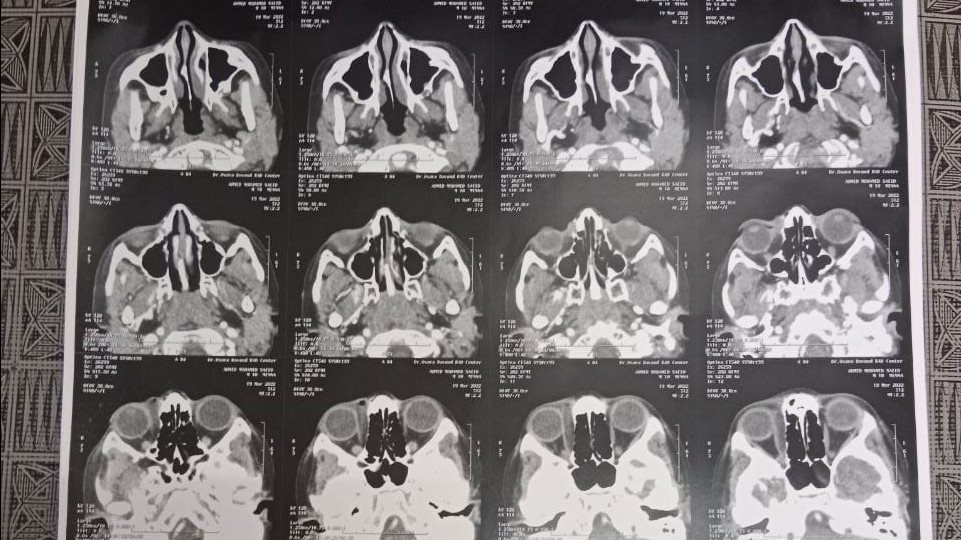

تابع وكيل الوزارة سير العمل، والخدمات الطبية المقدمة للمواطنين بالقافلة، وتفقد توقيع الكشف الطبي علي المرضي في التخصصات الطبية المختلفة والتي تشمل "الباطنة، الجراحة العامة، القلب، العظام، الأطفال، النساء والتوليد، الجلدية والتناسلية، تنظيم الأسرة، أنف وأذن"، وإجراء الفحوصات المعملية، والأشعات اللازمة، والكشف عن أمراض السكر والضغط، وصرف العلاج اللازم للمرضي مجاناً، وبلغ ما تم توقيع الكشف الطبي عليه أكثر من ١٢٠٠ مريض حتي وقت الزيارة.